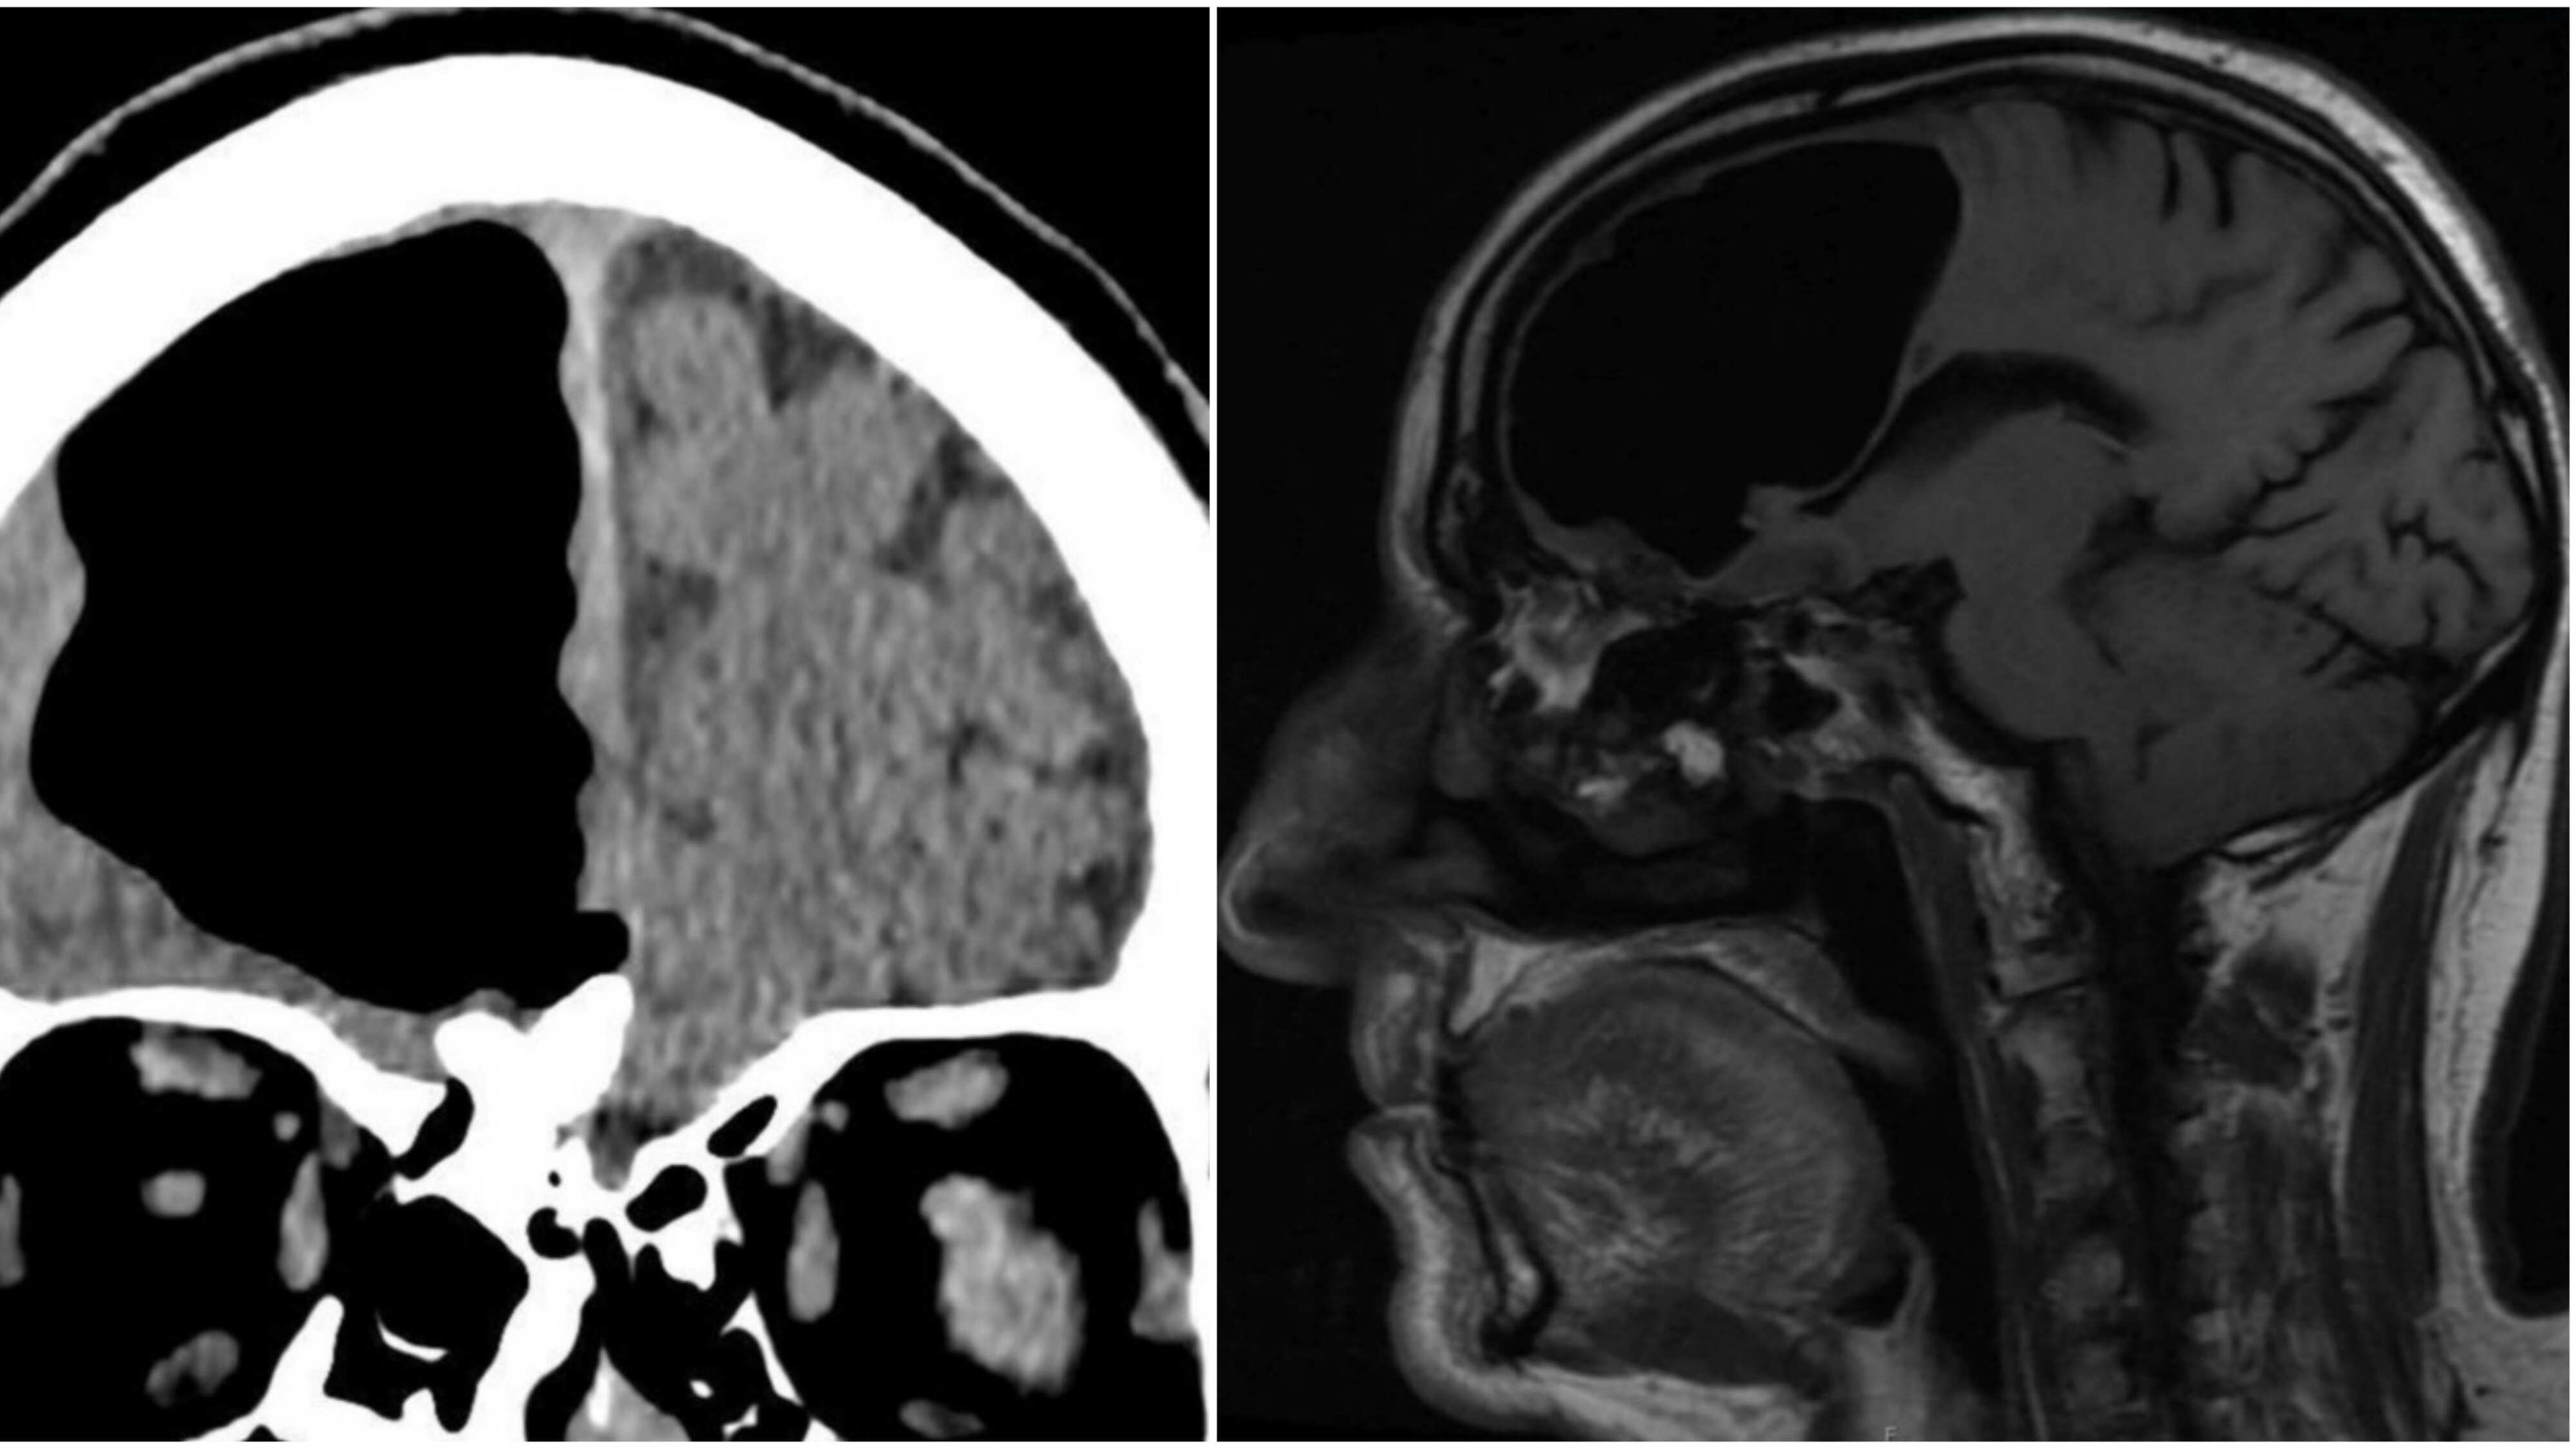

Los doctores no lo podían creer, pero los exámenes eran claros y mostraban una cavidad de aire de unos 9 centímetros en el lóbulo frontal derecho de un hombre de 84 años en el lugar donde debía estar su cerebro.

Tras ello, el hombre fue sometido a una tomografía computarizada y se encontraron con el increíble hallazgo.